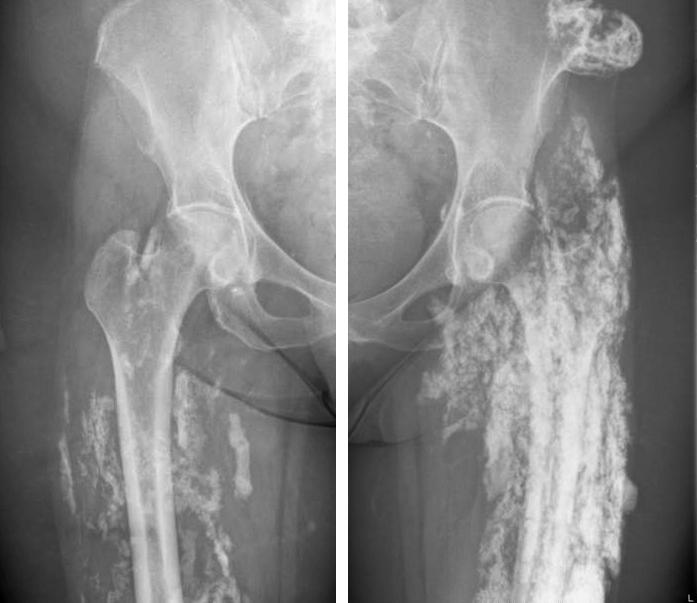

Een vrouw met chronische infectie van de bovenbenen

Een 58-jarige vrouw onderging 30 jaar geleden een liposuctie van beide bovenbenen. Sindsdien zijn er in de bovenbenen verhardingen ontstaan met chronische ontsteking, fistelvorming, pijn en een bewegingsbeperking.